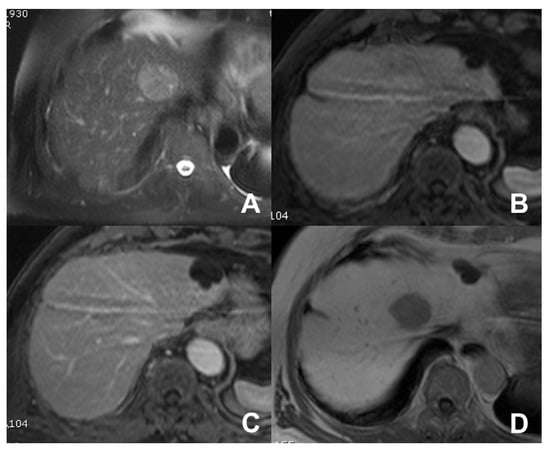

| Cirrhotic liver: characterization of FLL/Follow-up after treatment | HASTE T2 | AXIAL | -- | -- | Anatomy and liquids analysis |

| INDICATIONS: MRI is the technique of choice in young patients and pregnant women after a unclear US finding. Moreover, it is useful even after a CT with undefined diagnosis for all patients. | HASTE T2 | CORONAL | -- | -- | Anatomy and liquids analysis |

| DWI b 0–50–400–800 | AXIAL | -- | -- | High signal in b 800 suspicious for HCC | |

| GRE T1 IN/OUT | AXIAL | -- | -- | Steatosis | |

| GRE T1 3D DYNAMIC | AXIAL | PRE-ART 25″-PORTAL 70″-LATE 180″ | YES (if the lesion shows atypical enhancement) | Hypointensity in HBP suspicious for HCC | |